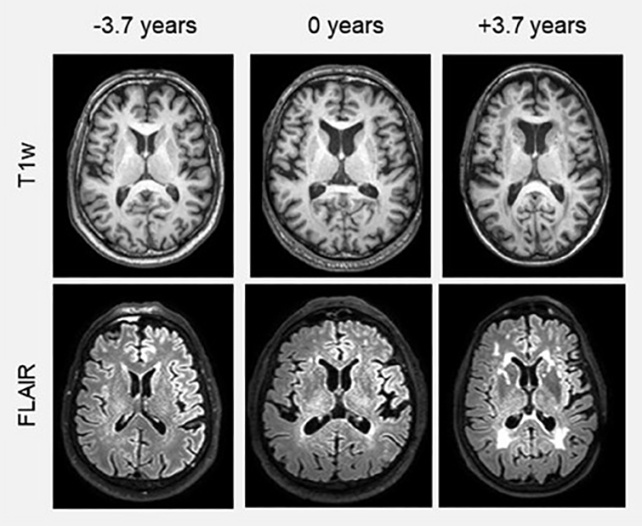

Для оценки возраста мозга по снимкам магнитно-резонансной томографии команда использовала модель искусственного интеллекта с глубоким обучением, предварительно обучив её на более чем 18 000 снимков людей без каких-либо когнитивных проблем.